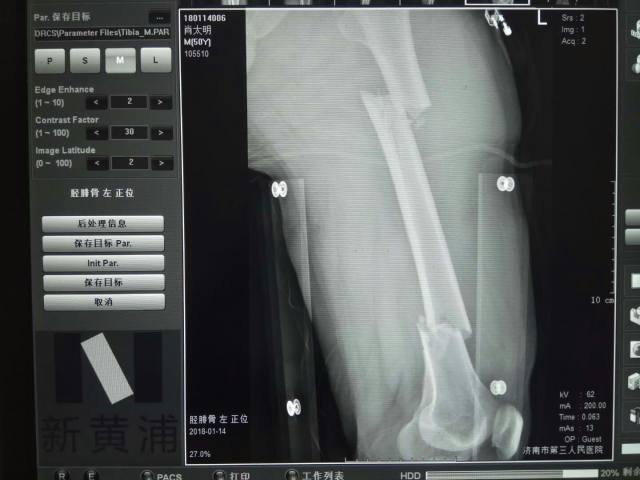

2018 年 2 月份,陈先生(化名)在车祸中受伤导致复杂股骨骨折,一根长骨断成几节,伤势严重,济南市第三人民医院创伤骨外一科主任谢新敏手术团队创新性地为其实施了「骨科机器人辅助下复杂股骨骨折闭合复位内固定术」,据查阅此例手术为山东省内首例。

如果采用传统髓内钉手术如闭合复位需透视下反复调整导针入针点、导针方向,术中放射损害大,手术时间长,髓内钉方向很难尽如人意。而机器人辅助下手术一次完成导针定位、置入,且导针入针点、方向近乎完美。术中透视次数也大大减少,手术出血、时间均较短。相比传统手术,骨科机器人辅助下闭合复位内固定术具有手术复位、固定精准,切口小、手术时间短,术中放射损害小,术后恢复快、副作用少的绝对优势。